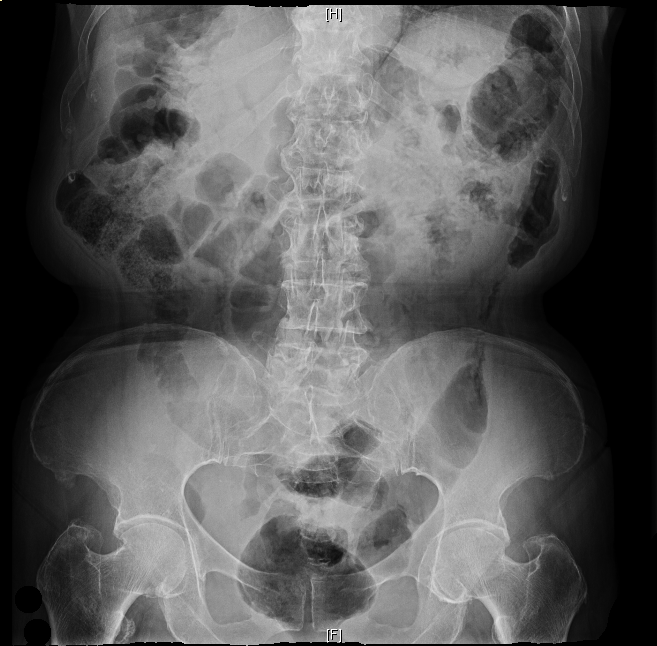

Rx de abdomen: El desafio

Mujer de 78 años que acude por epigastralgia desde hace una semana, inicialmente era sólo con la comida para ser constante con el correr de los días. Ha presentado nauseas sin vómitos y nos refiere que presentó una deposición diarreica hace unos dias, sin sangre ni moco. Con el interrogatorio nos comenta que hasta el año pasado iba de vientre en forma bastante regular, pero que desde hace como 6 meses se ha vuelto sumamente irregular. Y nos comenta que ha bajado de peso unos 4 Kgs. Como antecedentes personales HTA, DM II, DLP, Asma y una IQ por una eventración abdominal hace 7-8 años.

Su tratamiento habitual es Diamicron®, Metformina®, Enalapril, Higrotona® y Salbutamol a demanda.

Constantes: T 37 C, TA 135/87 mmhg, FC 78 lpm, y le solicitamos una Analítica, ECG y Rx de abdomen que nos trae a la semana. A la exploración física se aprecia dolor en forma difusa. Le prescribimos metamizol y aguardamos las pruebas complementarias.

Una semana después acude con un ECG: Rs 78 lpm, qrs estrecho sin alteraciones en la repolarización, una analítica: Hb 11,3 g/dl, VCM 78, Na 125 siendo el resto Normal, y una Rx de abdomen en bipedestación que os dejo para comentar y especular……el viernes la respuesta!